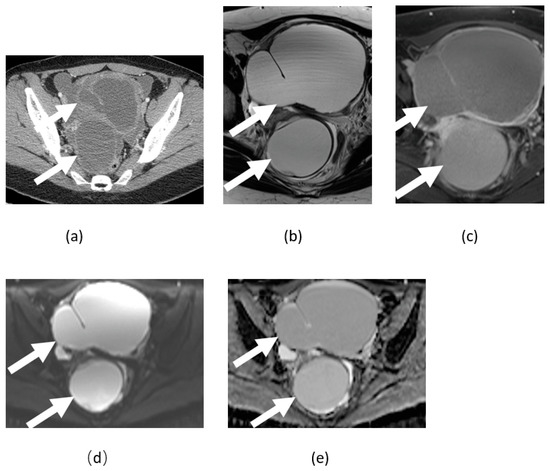

3.6. Ovarian Fibroma, Fibrothecoma, and Thecoma

- Chung, B.M.; Park, S.B.; Lee, J.B.; Park, H.J.; Kim, Y.S.; Oh, Y.J. Magnetic resonance imaging features of ovarian fibroma, fibrothecoma, and thecoma. Abdom. Imaging 2015, 40, 1263–1272. [Google Scholar] [CrossRef] [PubMed]

- Zhang, H.; Zhang, G.-F.; Wang, T.-P.; Zhang, H. Value of 3.0 T diffusion-weighted imaging in discriminating thecoma and fibrothecoma from other adnexal solid masses. J. Ovarian Res. 2013, 6, 58. [Google Scholar] [CrossRef] [PubMed]